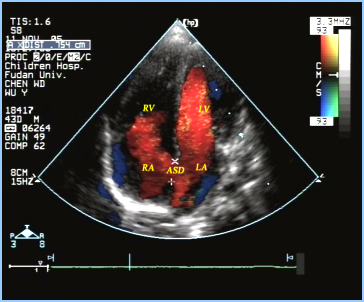

房间隔缺损:超声心动图表现

房间隔缺损(原发孔型)合并二尖瓣裂缺